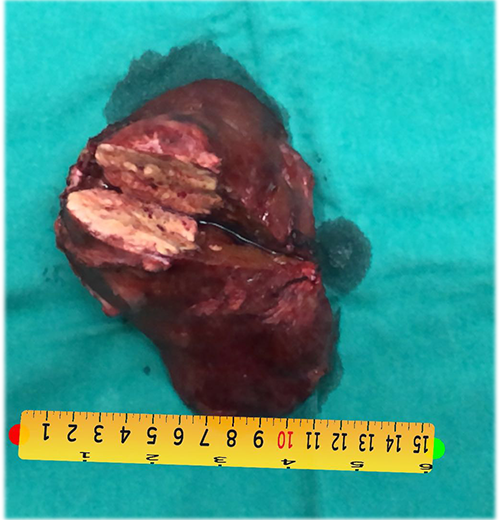

右肝癌复发-门静脉栓塞+肿瘤动脉栓塞后右半肝切除